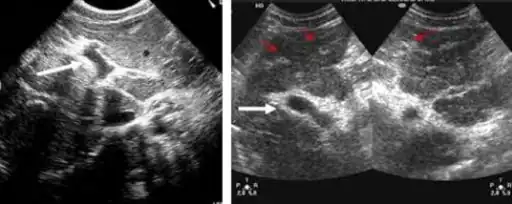

Ultrasonographic images in hepatic schistosomiasis

High-powered detailed micrograph of Schistosoma parasite eggs in human bladder tissue